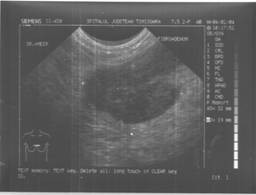

Teoretic invizibile la ecografie, sondele de frecventa inalta (peste 10MHz) permit vizualizarea microcalcificarilor. Ele sunt vizibile si cu frecvente de 7,5MHz cand sunt numeroase, grupate si daca sunt situate intr-o formatiune hipoecogena.

Confirmarea prezentei unei mase intr-o zona cu microcalcificari creste probabilitatea de leziune maligna de la 15-20% la 38%.zive. Ecografia nu imbunatateste calitatea analizei microcalcificarilor. In anumite situatii se poate dovedi utila pentru efectuarea de microbiopsii ecoghidate.